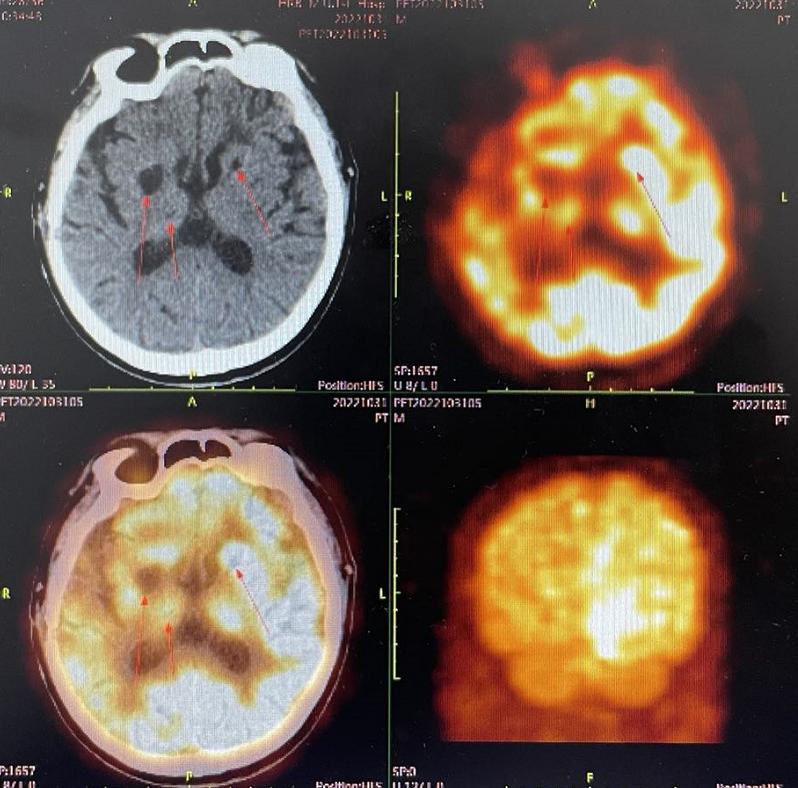

影像检查:.双侧颞叶、左顶、右侧基底节区异常强化,较前病变范围增大;多发脑梗死(包括脑干),部分陈旧软化;右侧基底节区陈旧出血灶;脑白质疏松;透明隔腔增宽